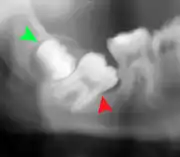

Coronectomy is a procedure where the crown of the impacted wisdom tooth is removed, but the roots are intentionally left in place. It is indicated when there is no disease of the dental pulp or infection around the crown of the tooth, and there is a high risk of inferior alveolar nerve injury.[31]

Coronectomy, while lessening the immediate risk to the inferior alveolar nerve function has its own complication rates and can result in repeated surgeries. Between 2.3% and 38.3% of roots loosen during the procedure and need to be removed and up to 4.9% of cases require reoperation due to persistent pain, root exposure or persistent infection. The roots have also been reported to migrate in 13.2% to 85.9% of cases.[31]